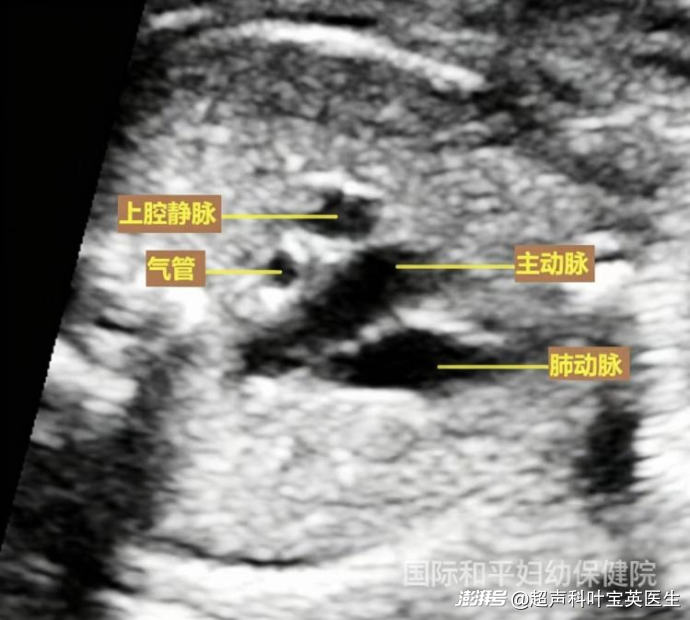

产前超声关键切面:三血管-气管切面(3VT)

正常表现:主动脉、肺动脉呈“V”形排列,气管位于上腔静脉后方(图2)。

图2 正常三血管-气管切面